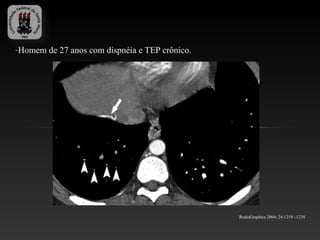

-Homem de 27 anos com dispnéia e TEP crônico.

RadioGraphics 2004; 24:1219 –1238